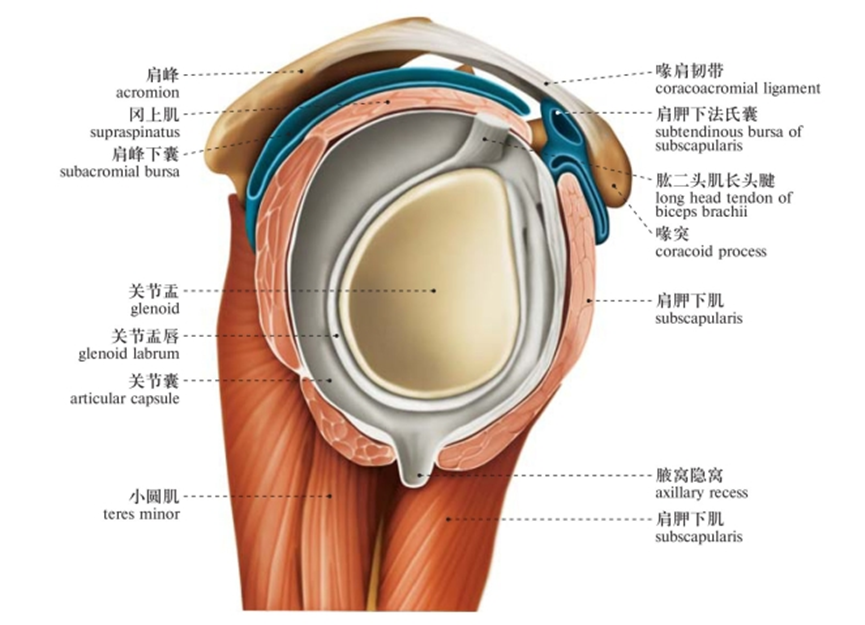

由肩胛骨的关节盂与股骨头组成,又叫肩肱关节(盂肱关节)。是典型的多轴球窝关节,为全身最灵活的关节,可作三轴运动,即冠状轴上的屈和伸,矢状轴上的收和展,垂直轴上的旋内、旋外及环转运动。

因肱骨头较大,呈球形,关节盂浅而小,仅包绕肱骨头的1/3,关节囊薄而松弛,所以是人体运动范围最大而又最灵活的关节。

这个结构上的特点虽然保证了它的灵活性,但它的牢固稳定性都较其他关节为差,是全身大关节中结构最不稳定的关节。

囊外:喙肱韧带、喙肩韧带及肌腱加强其稳定性。

唯有囊下部无韧带和肌加强,最为薄弱,故肩关节脱位是,肱骨头常从下部脱出,脱向前下方。

三角肌:起自锁骨外1/3、肩峰、肩胛冈,由三束组成,止于肱骨三角肌粗隆,由腋神经(C5—7)支配。作用:使肩关节外展、后伸和旋外、前屈和旋内。

小圆肌:起自肩胛骨外侧缘背面,止于肱骨大结节下部。由腋神经(C5—7)支配。作用:使关节旋外。

冈上肌:起自冈上窝,穿过肩峰和喙肩韧带,止于肱骨大结节上部部。由肩胛上神经(C5—6)支配。作用:使肩关节外展。

冈下肌:起自冈下窝内,止于肱骨大结节中部。由腋神经(C5—7)支配。作用:使关节旋外。

肩胛下肌:起自肩胛下窝(肩胛骨前面),止于肱骨小结节。由肩胛下神经(C5—6)支配。作用:使肩关节旋内、内收。